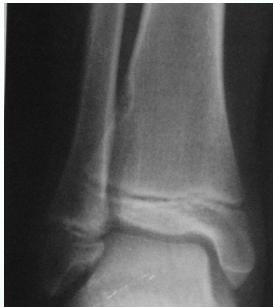

Comparison of Cyst-Like Lesions in Bone

Simple Bone Cyst

- Fills medullary cavity

- Does not expand bone

Aneurysmal Bone Cyst

- At metaphyseal side of physis

- Expansile

Giant-Cell Tumor

- After fusion of physis

- Extend to sub-articular